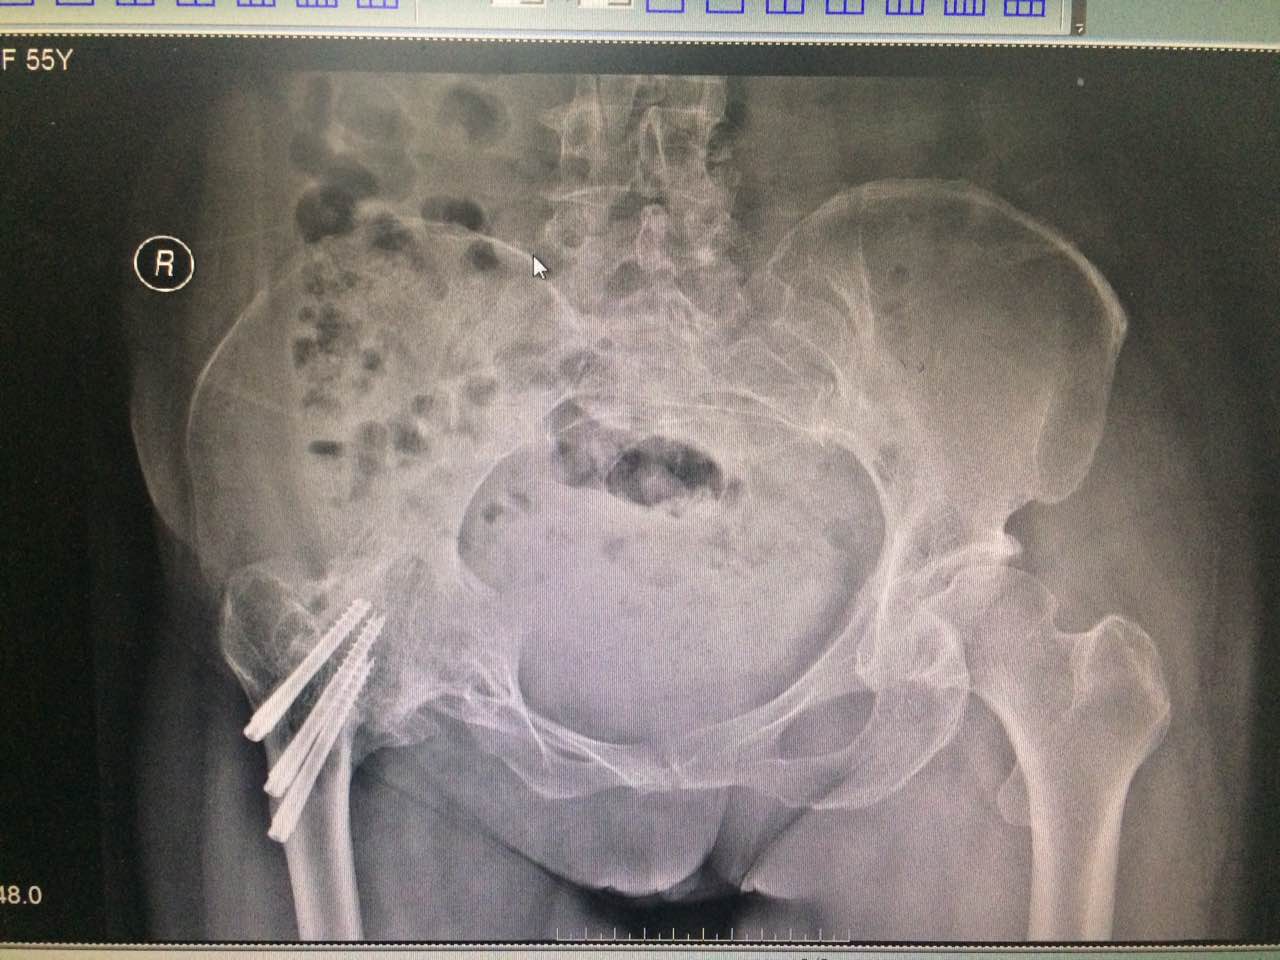

患者马某,女,55岁,三年前因骨折后行右髋关节切开复位内固定手术,术后间断性酸困,遇劳加重,渐出现右髋关节僵硬,活动受限,在附近区医院给予保守治疗(具体不详),于2017年3月来诊。经弧刃针标准疗法(火灸、弧刃针、臭氧、药物等)治疗后,疼痛明显缓解,活动度改善,特送来锦旗,以表感谢!